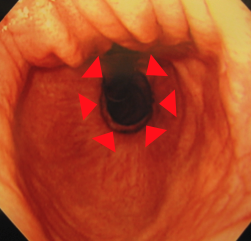

食道と胃のつなぎ目はしっかりと締まっています。

もちろん、逆流もありません。

しっかりとした“襟巻き”が出来上がっています。

ひどかった食道炎も改善しています。